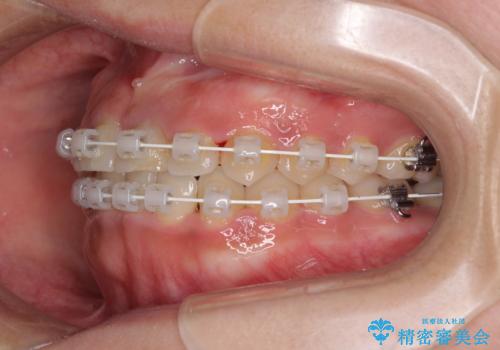

前歯の反対咬合 非抜歯のワイヤー矯正

- 審美装置

マウスピース矯正の自己管理が面倒くさいことと、治療を早く終わらせたいとのことで、目立ちにくいワイヤー矯正にて歯列を整えることとしました。

1年半はかかると思っていた治療期間ですが、反対咬合となっている前歯が思いの外早く動き、僅か9ヶ月で終了させることができました。